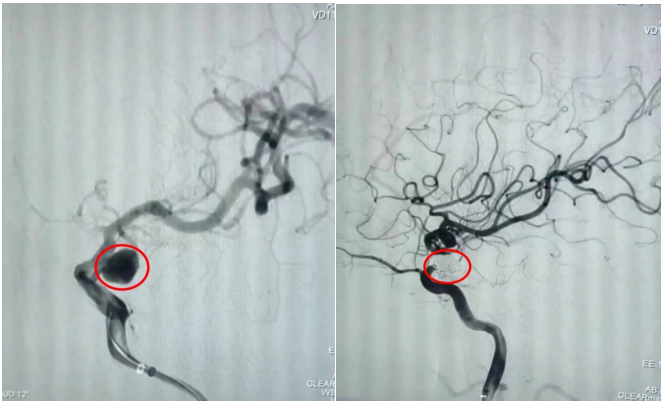

通訊員劉洋、劉立君報(bào)道: 9月2日家住衡山縣的劉爺爺從衡陽市中心醫(yī)院神經(jīng)內(nèi)科出院了。劉爺爺8月22日因左側(cè)頸內(nèi)動(dòng)脈后交通段動(dòng)脈瘤破裂致蛛網(wǎng)膜下腔出血,病情危在旦夕,在衡山縣人民醫(yī)院行急診全腦血管造影明確病因后,連夜轉(zhuǎn)入衡陽市中心醫(yī)院神經(jīng)內(nèi)科治療。衡陽市中心醫(yī)院神經(jīng)內(nèi)科介入團(tuán)隊(duì)立即接手病人,經(jīng)過認(rèn)真查看病人、細(xì)致分析病情,聯(lián)合介入室、麻醉科為病人緊急行動(dòng)脈瘤介入栓塞術(shù),手術(shù)順利,術(shù)后通過腦脊液置換、預(yù)防腦動(dòng)脈痙攣、預(yù)防深靜脈血栓、預(yù)防感染等綜合治療措施,緩解了劉爺爺?shù)念^痛癥狀,避免了并發(fā)癥的發(fā)生,10天后劉爺爺又回到了衡山縣人民醫(yī)院進(jìn)行后續(xù)康復(fù)治療。